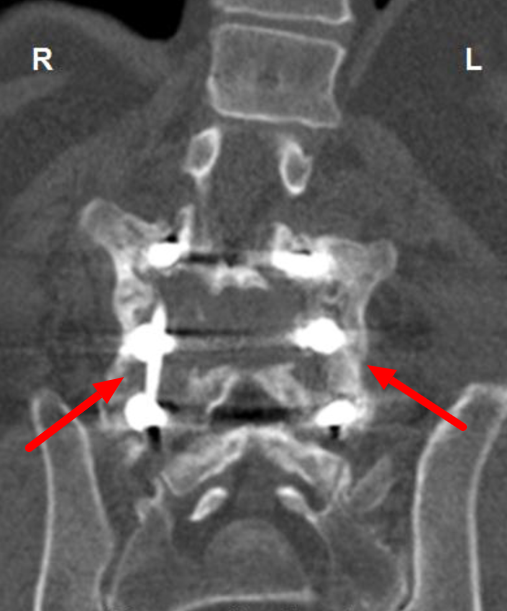

posterior spinal fusion and instrumentation show two spinal rods and segmental pedicular screws What Is A Long Spinal Fusion  A minimally invasive spinal fusion uses a smaller cut (incision) than a. A spinal fusion is a common type of complex spinal surgery that can help with chronic back pain in certain situations. Spinal fusion is a procedure that permanently joins two vertebrae into one solid bone. Spinal fusion is a surgery procedure that reinforces your back structure and stability. What Is A Long Spinal Fusion.